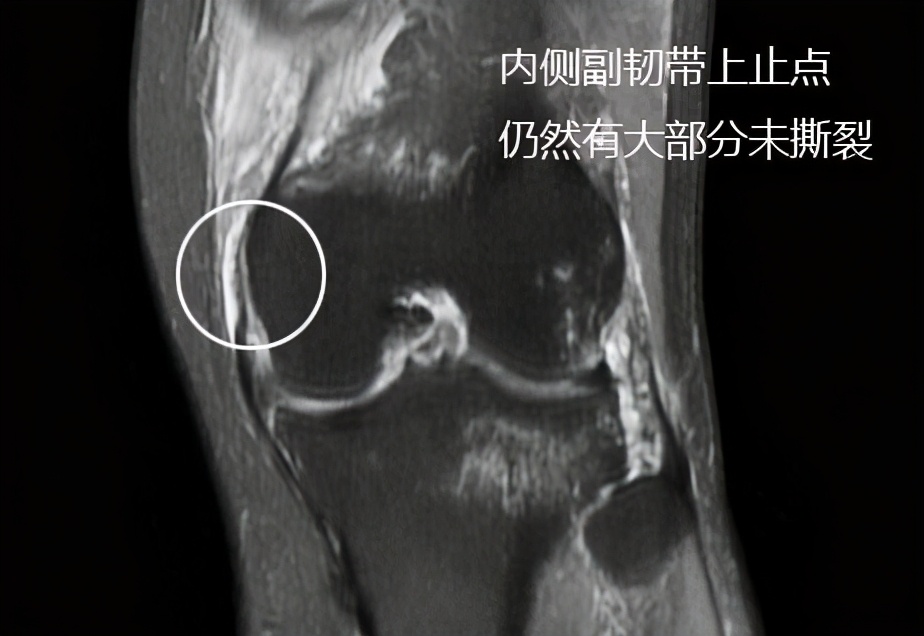

老爷子的核磁与预估得差不多,但是有它的特殊之处,在查体的时候,我们发现老爷子关节内侧方向的稳定性并不是特别的好,本以为是内侧副韧带发生了较大撕裂,但是在核磁上我们发现内侧副韧带损伤相对来讲不是特别的严重,而内侧肌肉撕裂相对来讲比较明显。

选择:内侧副韧带是维持我们关节内侧方向稳定非常重要的一个结构,在这位老人的核磁影像上,评估撕裂应该在30-45%左右,有保守的价值;对于内侧肌肉的撕裂,虽然在核磁上看起来水肿比较明显,但是这种损伤我们可以考虑给予进行保守治疗,以往有几例同样损伤的患者,谢医生给予进行了保守治疗,都获得了比较好的效果,毕竟肌肉损伤不是那种完全的撕裂,相比韧带的完全撕裂恢复起来真的要快很多,所以关于内侧的不稳定,应该尝试保守治疗,给予支具固定,局部冰敷,适度外用消炎镇痛药,指导康复锻炼即可。